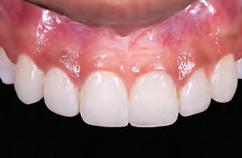

A 31-year-old woman presented with cosmetic concerns regarding her smile and requested a conservative enhancement. After clinical and radiographic analysis, digital 35mm photographs were taken and reviewed by the restorative clinician, technician, and surgeon (Fig 1). A digital impression was taken of the maxillary and mandibular arches using an intraoral scanner (Trios 3, 3Shape; Fig 2), and a smile design was developed with NemoSmile Design 3D software (Nemotec; Fig 3a). This allows for a facially driven smile frame to be created using reference lines of facial and smile proportions and natural teeth shapes and textures from the digital library (Fig 3b).

After developing the simulated mock-up, a 3D-printed resin model was created using CAD software (Fig 4a), and a clear PVS matrix (Exaclear, GC America) was fabricated to replicate the printed diagnostic wax-up using a nonperforated tray (Fig

Fig 1 Preoperative clinical views of a 31-year-old woman presenting with diastemas and limited tooth visibility. (top) Portrait. (center row) Intraoral views. (bottom row) Smile.

4b). This matrix was used to create an intraoral motivational mock-up with bis-acryl composite (Luxatemp Ultra, DMG). This additive mock-up provides the interdisciplinary team with an intraoral translation for evaluation (Fig 5). Upon evaluation of the digital smile frame and the clinical translation, it was determined that multiple esthetic and restorative requirements were necessary for an optimal biologic framework, and the interdisciplinary team determined the best sequence for these procedures. The patient was presented with the interdisciplinary treatment possibilities that included restoring the maxillary anterior teeth and premolars with a minimally

invasive preparationless procedure or with less conservative veneer preparations. The restorative materials discussed included injectable resin composites and ceramic (ie, feldspathic, pressable, machinable). For an optimal biologic framework and health, it was determined that connective tissue grafting would be necessary for treatment of the recessiontype defects on the maxillary left central and lateral incisors, canine, and premolars. The patient opted for the conservative preparationless composite veneers using the injectable resin technique followed by a connective tissue surgical procedure using the tunneling technique.